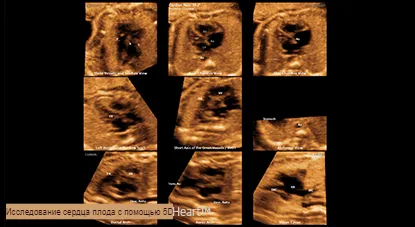

5D HeartTM Функция обеспечивает 9 стандартных плоскостей сердца, используя данные STIC плода, а также важную информацию о развитии сердца плода простым и точным способом в соответствии с рекомендациями AIUM.